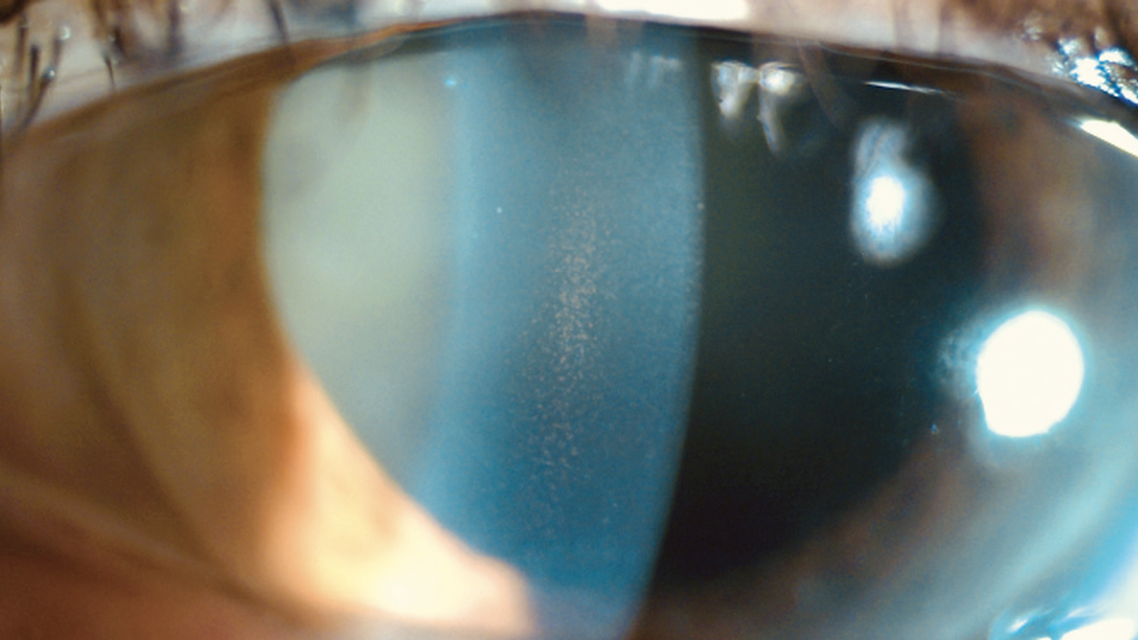

Pigmentary dispersion syndrome (PDS) is characterized by anatomic variation of the iris and lens, which creates increased friction between these structures. This leads to pigment liberation and the creation of the medical triad of PDS;1 specifically, Krukenberg spindle (Figure 1), radial midperipheral iris transillumination defects (Figure 2), and pigment accumulation in the trabecular meshwork.1